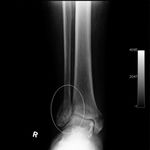

This 65-year-old insulin-dependent diabetic sustained a fracture of his right ankle in 2010 and had an open reduction internal fixation which failed due to problems with his healing. He went on to have a complete collapse of the right ankle and sought opinions on the options for him.

He was diagnosed as having a Charcot's Joint i.e. due to his diabetic status, he lost sensation in the foot and ankle area which eventually led to a collapse of the foot and ankle and resulted in poor wound healing and bone repair. These all led to his poor outcome from his primary surgery.